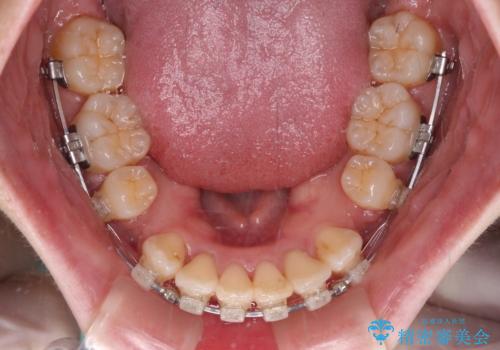

- クリアブラケット

- 前歯の出っ歯と口元の閉じにくさを気にして来院された患者様です。

口元を積極的に引っ込めるために、上下左右の小臼歯4本を抜歯し、目立たないワイヤー装置にて矯正治療を行うこととしました。